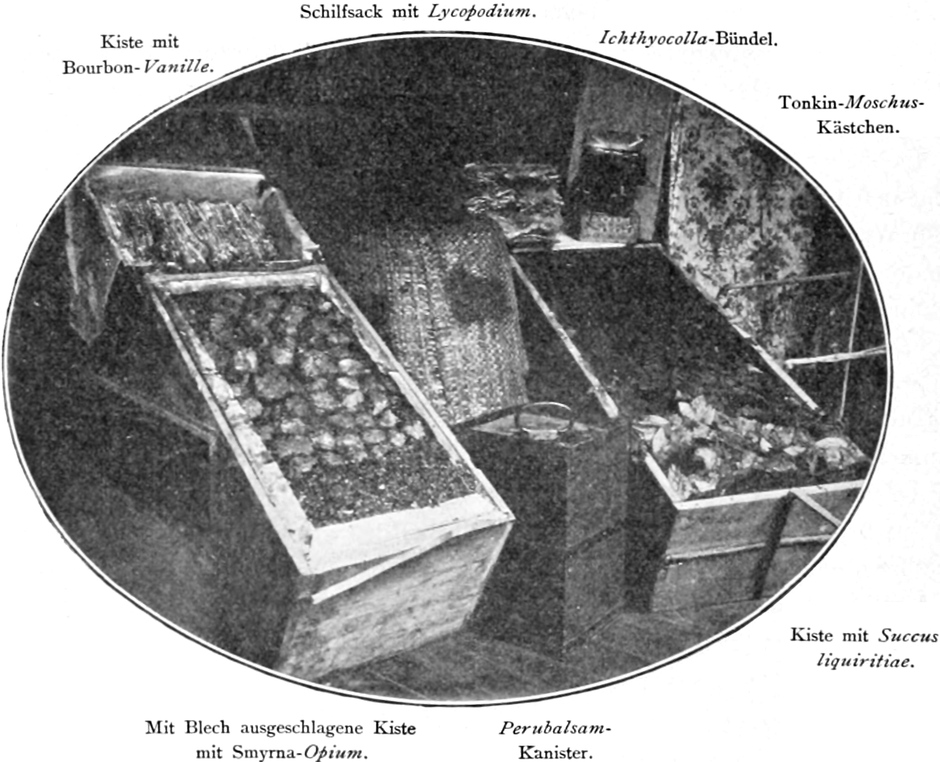

Zur Kennzeichnung der ausgestellten Waren und Gerätschaften auf den Tafeln XXX und XXXI waren im Original die betreffenden Bezeichnungen auf ein Deckblatt aus transparentem Papier gedruckt. In der vorliegenden Fassung wurde die Beschriftung vom Bearbeiter direkt in die Abbildungen eingefügt.